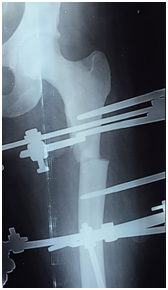

After spinal anesthesia was administered, she was placed on a traction table and under an image-intensifier a closed manual reduction was attempted to reduce the displacement as much as possible. But as expected, the proximal segment was significantly displaced upward- flexed and externally rotated. The decision was made to apply the ICD framework, and use the components to reduce the fracture- a benefit of the ICD system. 1.8 millimeter Russian made biocompatible olive wires and 5.0 millimeter tapered schanz pins were inserted based on the safe zones followed by the rings and arches. The initial deformity was well reduced in the coronal plane but was unsatisfactory in the sagittal plane. Taking into account the duration of the injury-specifically the contracted surrounding muscles, we applied a translation device for a gradual and controlled reduction. This also prevented the necessity of an open reduction, thus minimizing operative time, preventing blood loss, and the risk of fracture propagation if we had tried re-manipulation. Post-operatively the limb was clinically well-aligned (Figures 1 & 2).

Figure 1 Immediate postoperative radiograph in the coronal view showing a mild coronal and roational displacement.

Figure 2 Immediate postoperative radiograph in the sagittal view showing a significant displacement.